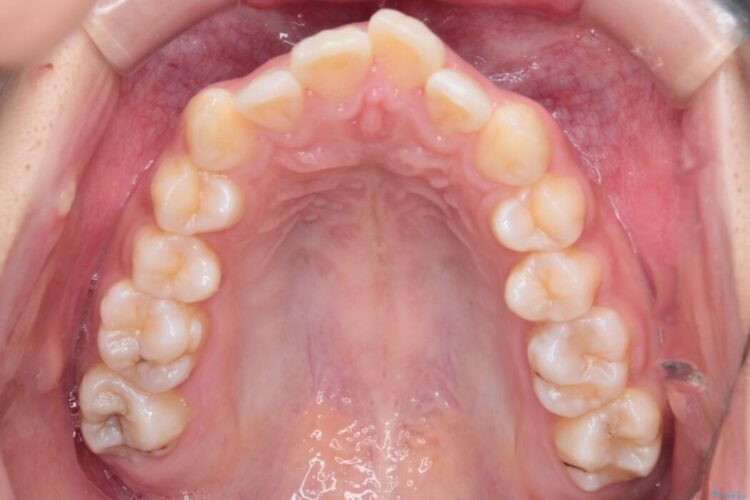

前歯から奥歯にかけて重度のがたつきを主訴にご来院された患者様です。

スペースが大きく不足し、口元を引っ込める必要があったため、上下左右4本抜歯による矯正治療を計画。目立たないインビザライン装置で、審美的なゴールを目指します。